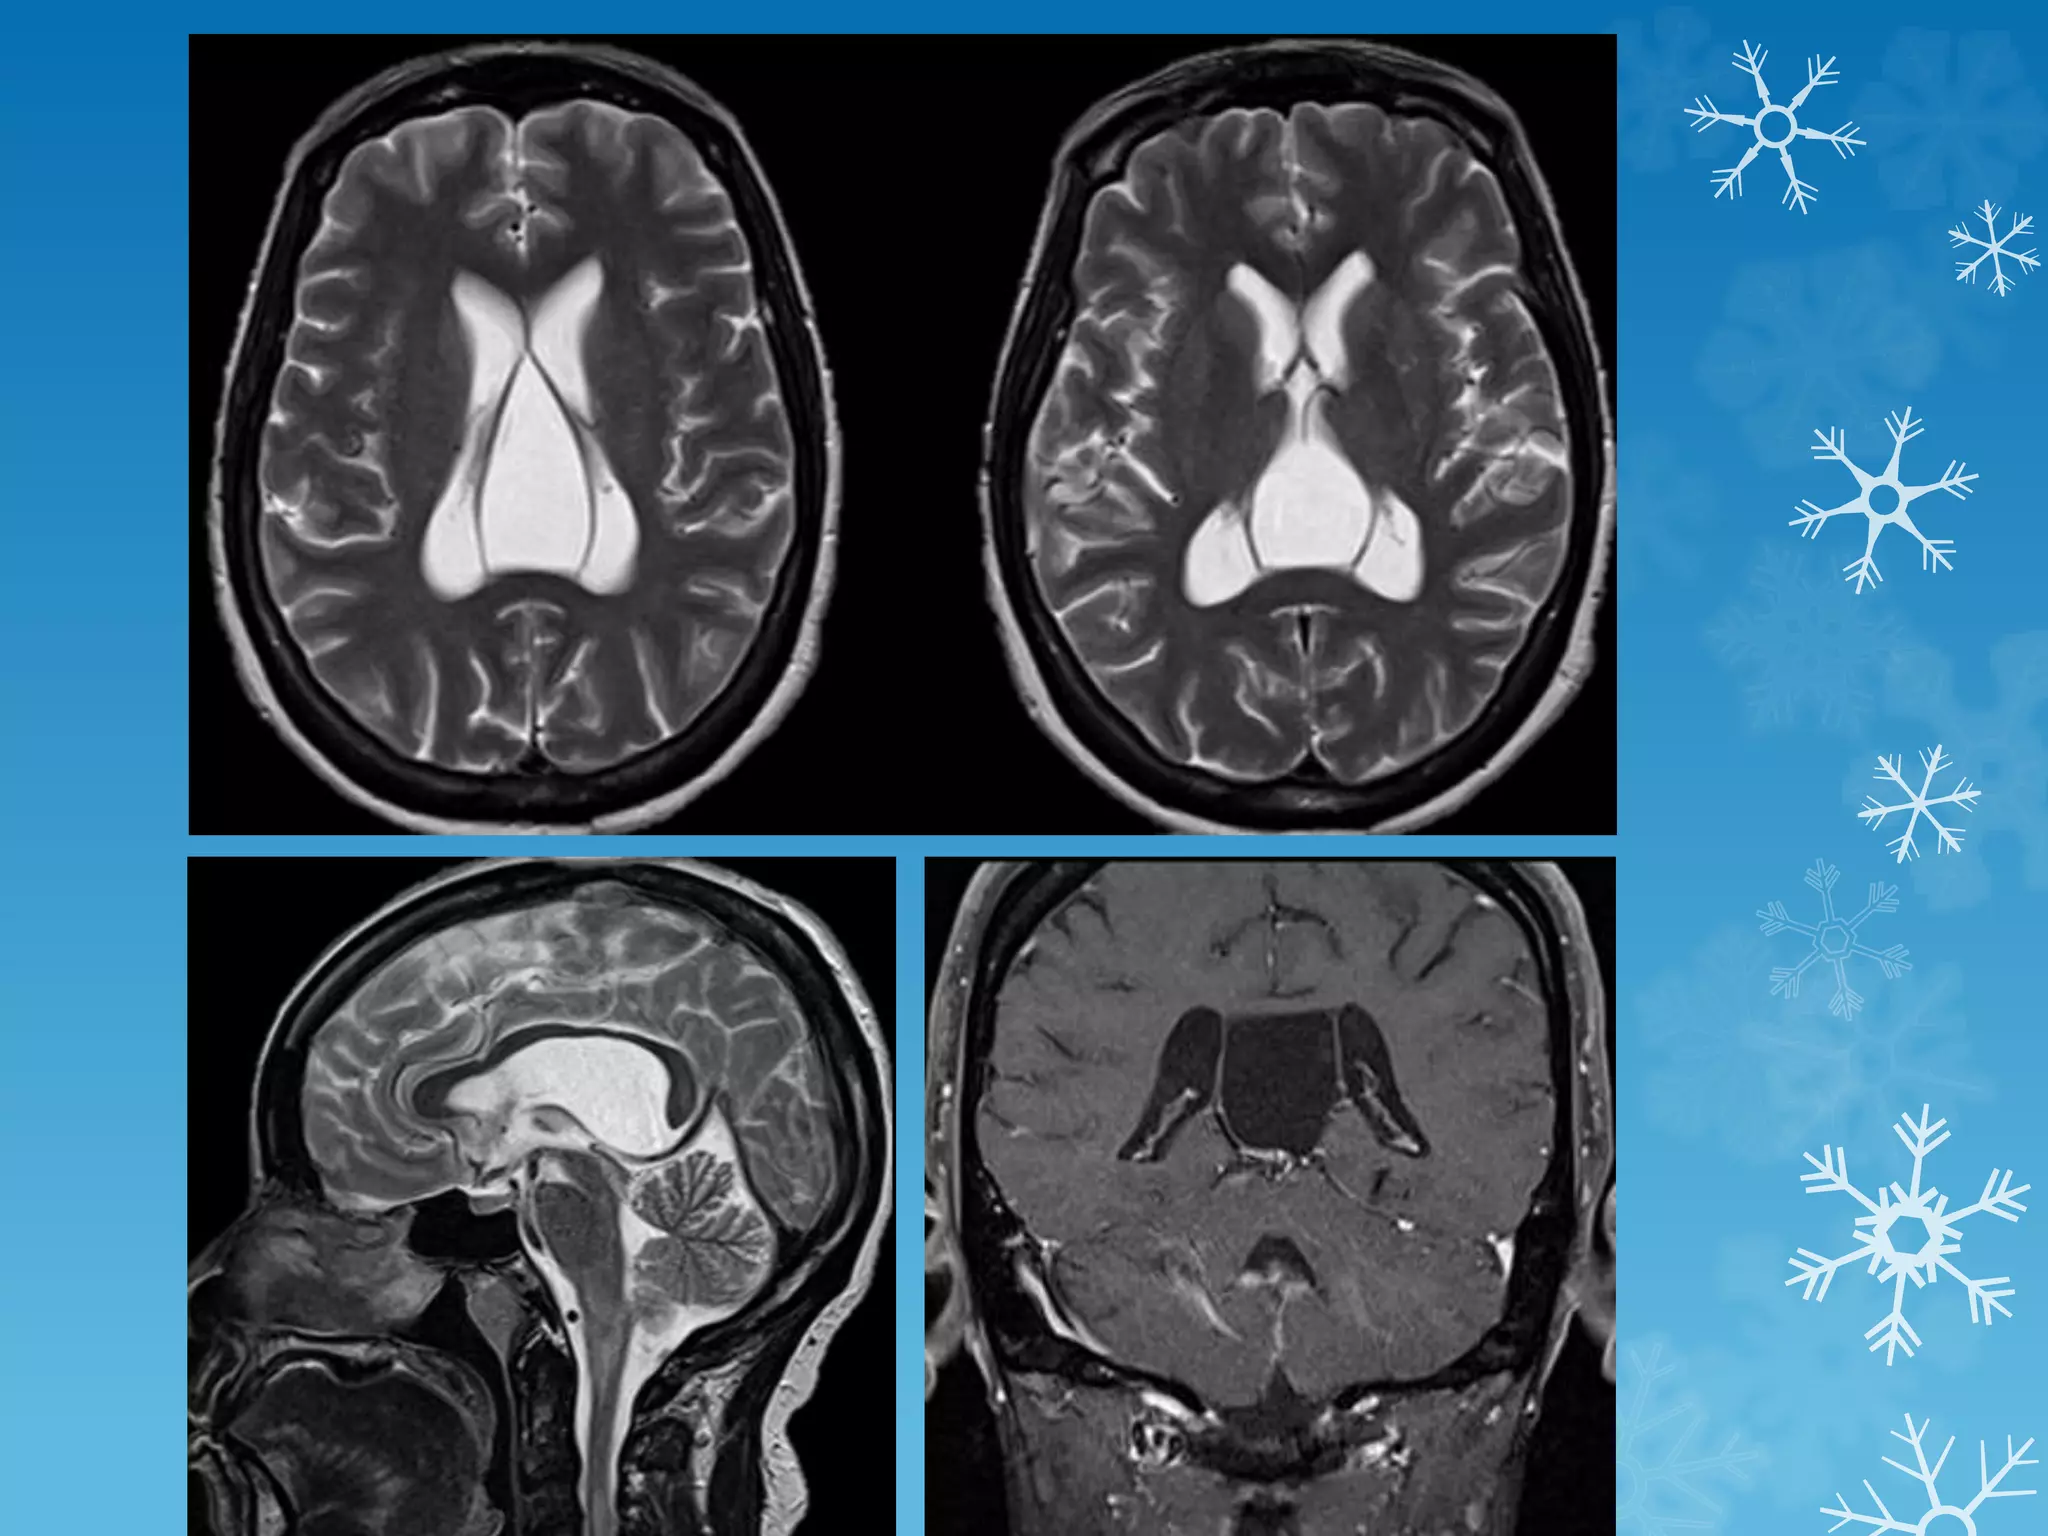

Band heterotopia

Cavum velum interpositum